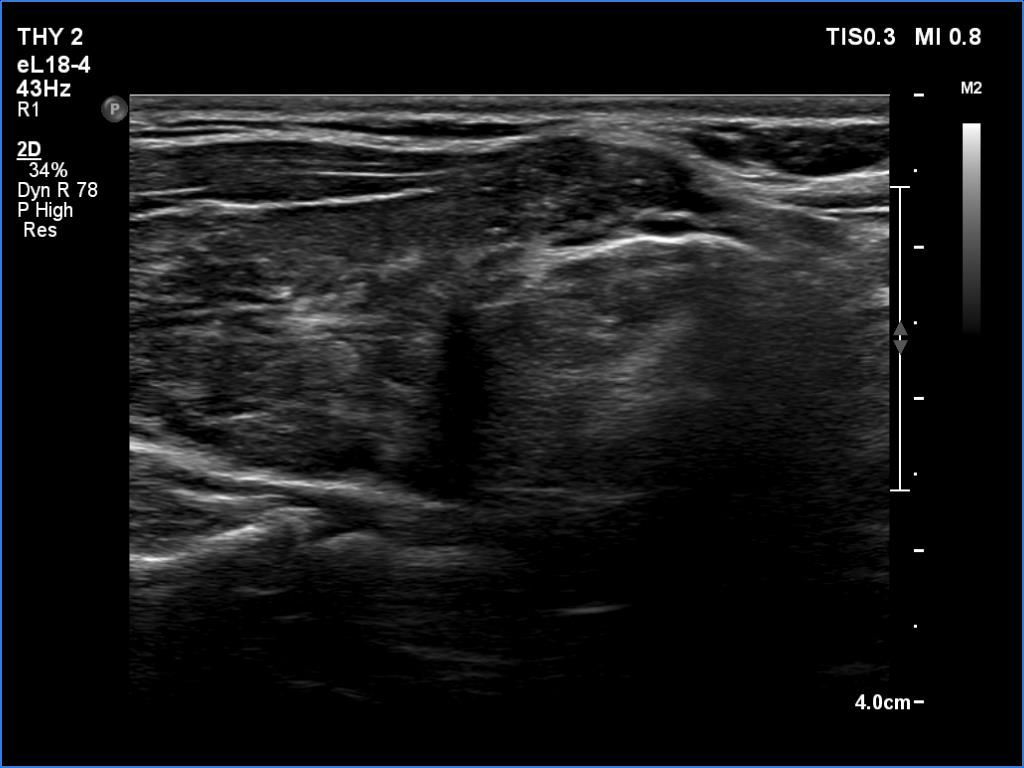

Ultrasonography. The thyroid was moderately hypoechoic and inhomogeneous. There was a deeply hypoechoic lesion in the isthmus which presented microcalcifications. Compared with the extranodular tissue, the nodule was much less vascularized on Doppler and microflow imaging but was harder on elastography.

There were two conditions which favored that the discrete lesion in the isthmus is a true nodule and not a more active focus of the underlying Hashimoto's thyroiditis. Firstly, the palpation which itself was suspicious of a cancer. Second, the presence of microcalcifications. It is worth comparing the similarly deep hypoechoic areas in the left lobe with the presentation of the cancer focus.